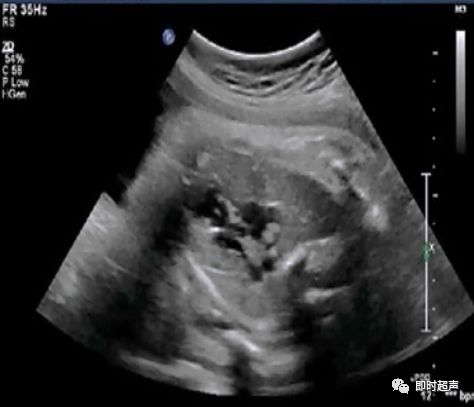

探到胎儿四腔心后,探头稍向胎儿头侧偏移即可显示三血管-气管切面,正常三血管-气管平面从左到右依次显示:肺动脉、主动脉弓、气管、上腔静脉。

胎儿三血管气管切面

三血管-气管切面的观察内容

- 从左到右依次是肺动脉、主动脉弓和上腔静脉

- 内径从左到右依次递减

- 主动脉弓位于气管的左侧

- 肺动脉和主动脉弓血流都流向脊柱,呈后向血流

- 肺动脉经动脉导管与主动脉弓共同汇入降主动脉